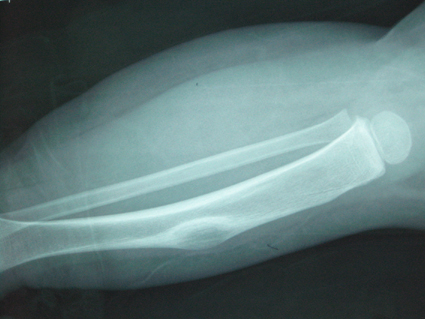

以下是引用黑白光影在2008-12-17 21:57:00的发言:[br]考虑骨纤维异常增殖症,不排除非骨化纤维瘤。

以下是引用zsl6918在2008-12-18 4:25:00的发言:[br]考虑骨纤可能性大